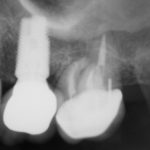

Erin

This patient had a implant place to replace a tooth which had been removed due to infection.